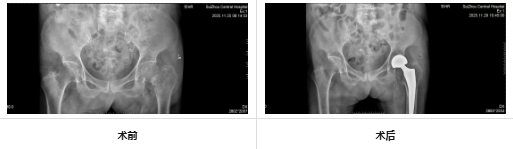

在充分的術(shù)前準(zhǔn)備與精細(xì)的術(shù)中操作下,團(tuán)隊(duì)成功為患者實(shí)施人工髖關(guān)節(jié)置換術(shù)。手術(shù)時(shí)間短、出血少,極大減輕了患者身體負(fù)擔(dān)。術(shù)后,在護(hù)理團(tuán)隊(duì)的精心照護(hù)與康復(fù)指導(dǎo)下,老人恢復(fù)良好,疼痛顯著緩解,生活質(zhì)量大幅提升。看著老伴重露笑容,老先生感激滿懷。